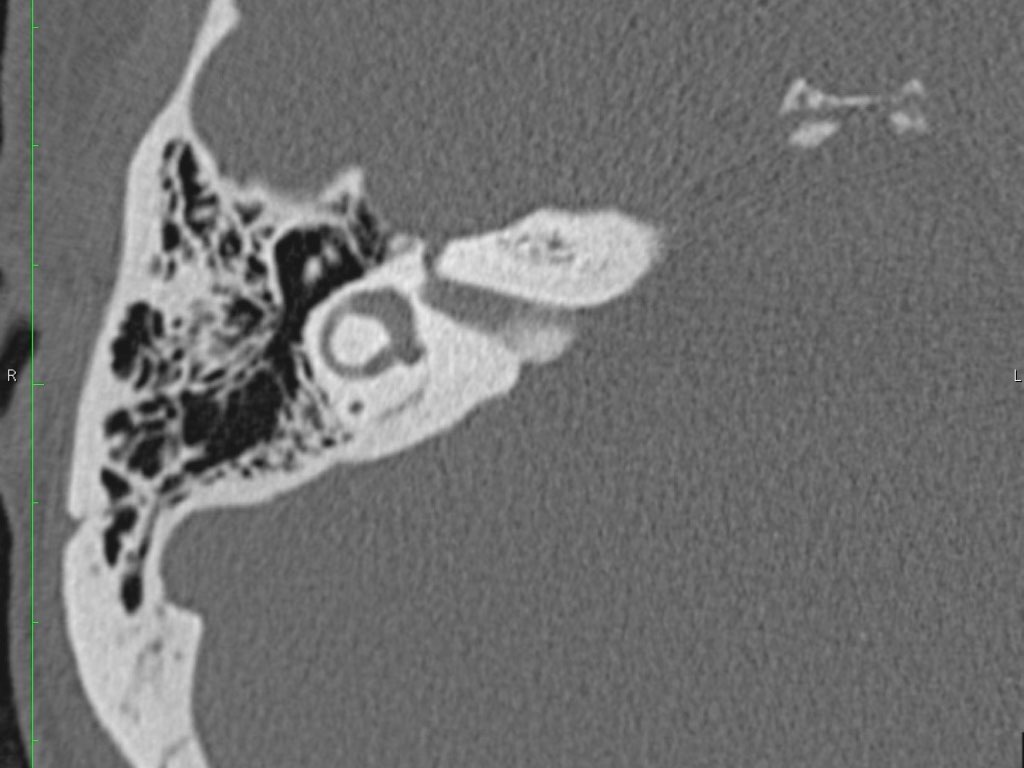

Thông qua ngách thượng nhĩ (aditus ad antrum), hòm nhĩ thông với hang chũm — một tế bào khí lớn nằm phía trên và phía sau hòm nhĩ — và thông với các tế bào khí chũm.

Hang bào chũm là một tế bào khí lớn nằm phía trên và phía sau hòm nhĩ, thông với hòm nhĩ qua ngách hang (aditus ad antrum).

Đoạn mê nhĩ của dây thần kinh mặt xuất phát từ ống tai trong, chạy gần như vuông góc với trục dài của xương đá, gập góc nhọn về phía trước để đến hạch gối (geniculate ganglion).

Tại hạch gối, dây thần kinh mặt tạo thành một khúc quặt hình chữ U (genu thứ nhất của dây thần kinh mặt) để chạy ra phía sau theo đoạn nhĩ dọc theo thành trong của thượng nhĩ.